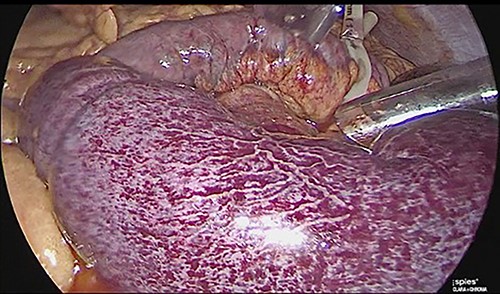

The patient was reoperated by laparoscopy, finding segmental thrombosis from 200 cm to 50 cm of the Treitz ligament, with edema and interloop free fluid without perforation (Figs 3 and 4). Lateral resection and entero–entero anastomosis were performed with manual stapler, subtracting 440 cm of intestine with adequate coloration. Later he was admitted to the Intensive Care Unit, treated with low molecular weight heparin at a full anticoagulation dose, maintaining an INR of 2 and a partial thromboplastin time of 80 s. He presented adequate evolution starting a liquid diet on the fourth postoperative day, new laboratories reported hemoglobin of 11 g/dl, 12 700 leukocytes/mm3, platelets 225 000/mcL, INR of 2. He was discharged on the fifth day with rivaroxaban treatment for 6 months.

Laparoscopic view of intestinal thrombosis 200 cm at the level of the proximal jejunum, 50 cm from the ligament of Treitz.

Laparoscopic view of intestinal thrombosis and free fluid in the cavity.